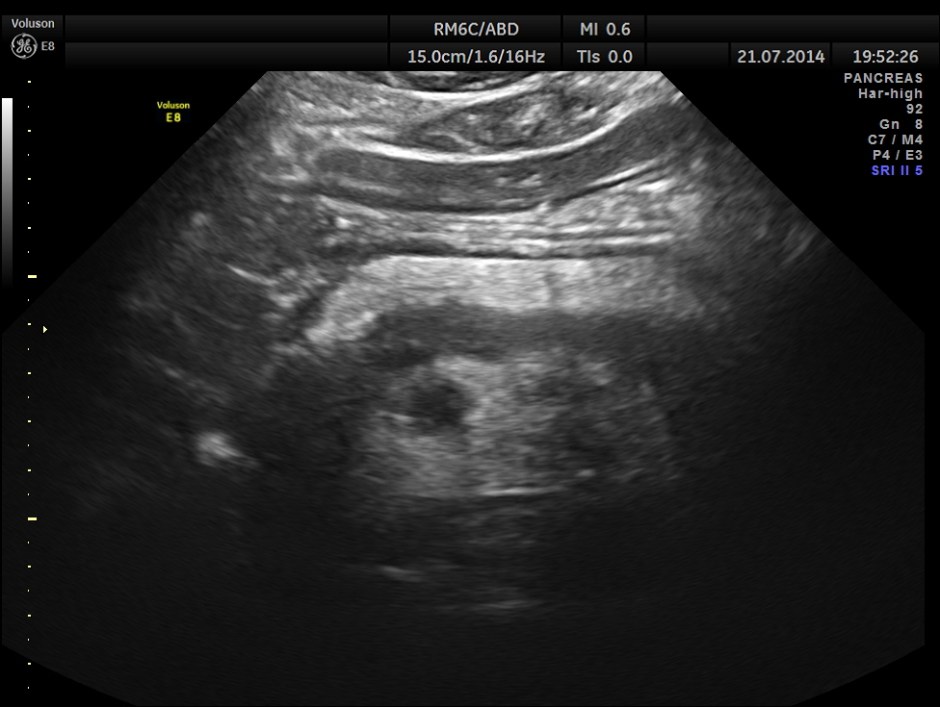

The following pictures show the pancreas.

Pancreatic duct is dilated prominently.

Pancreatic duct dilated.- 12.9 mms.

Pancreatic calculi are seen.

This patient further underwent Upper G.I. endoscopy , which was normal and later MRI scan , which confirmed the ultrasound findings. He was conservatively managed and is clinically better.